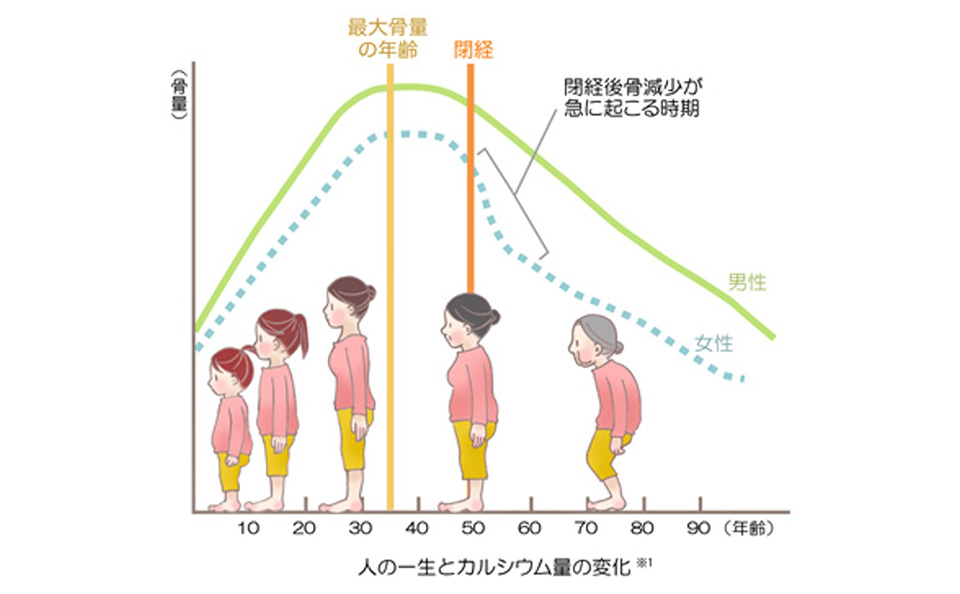

⾻塩定量検査部⾨

骨塩定量検査とは、骨組織の骨量が加齢と供に減少し、腰や背中の痛み・骨折などを起こしやすくなる骨粗しょう症の診断を主に行う検査です。X線を照射し直接骨量を測定するDEXA(デキサ)法で腰椎・大腿骨などを撮影して骨量を測定します。今年度(令和5年)、新たに東洋メディックの「Horizon」という装置を導入しました。これにより、今までよりも高精度な骨塩定量検査が可能となっています。